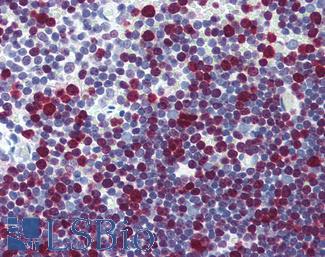

MSH6

Anti-MSH6 antibody IHC staining of human testis. Immunohistochemistry of formalin-fixed, paraffin-embedded tissue after heat-induced antigen retrieval. Antibody LS-B10739 dilution 1:50.